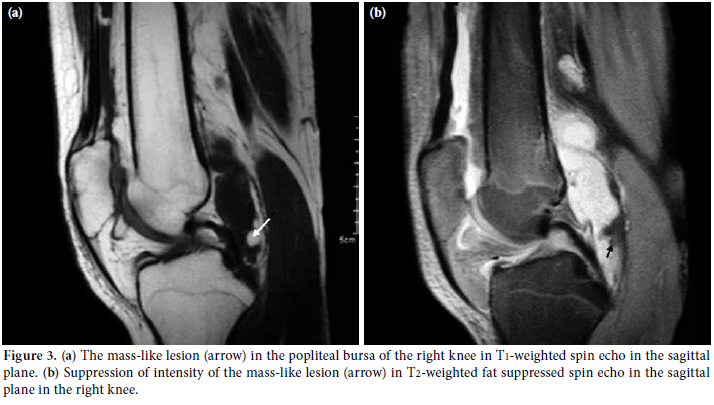

Magnetic resonance imaging revealed a large effusion and numerous frond-like projections which were prominent in the suprapatellar compartment of right knee. The intensity of these frond-like synovial projections, which were suppressed in fatsaturated sequences, was similar to the intensity of fat (Figures 2a, b). An effusion and a mass-like lesion were also detected in the popliteal bursa of the right knee. (Figures 3a, b) In addition, mild osteochondral changes occurred in both knees which were more pronouced on the right side (Figure 2a). Suprapatellar effusion was also detected in the left knee. No meniscal or ligament pathology was detected in either knee.

The presence of the large effusion and the numerous frond-like synovial projections in conjunction with the mass-like lesion, the intensity of which was suppressed in fat- saturated sequences in the right knee, led us to the diagnosis of LA. Since the MRI of the left knee did not meet the criteria for the LA diagnosis, the patient was referred to the orthopedics department for a surgical synovectomy of the right knee and for diagnosis of the problem in the left knee. During preoperative evaluation, echocardiography revealed atrial septal defect and the patient was referred to pediatric cardiology department for further evaluation.